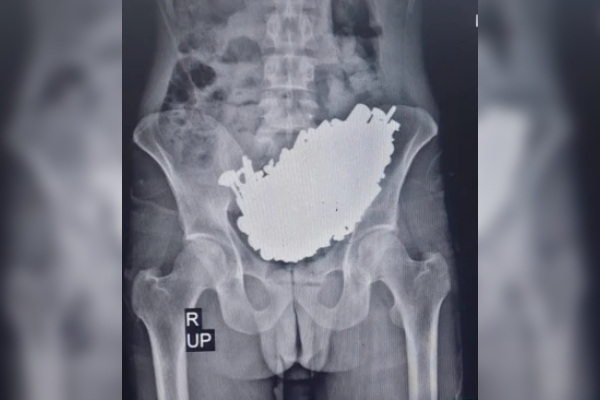

Foto: Journal of Medical Case Reports

Según una publicación de la revista Journal of Medical Case Reports, en la ciudad iraní de Ahvaz, un grupo de médicos logró extraer quirúrgicamente aproximadamente tres kilos de objetos metálicos del estómago de un paciente.

De acuerdo con los médicos, el paciente, un hombre de 36 años, llegó con dolor abdominal fuerte y vómitos. Después de llevar a cabo las pruebas, se determinó que se trataba de una obstrucción gástrica por varios objetos metálicos desconocidos.

Tras la operación, los médicos extrajeron alrededor de 450 objetos metálicos del estómago del hombre. Se trataba de tornillos, tuercas, llaves y piedras, que juntas dieron un total de 2.9 kilogramos. Días después, el paciente fue trasladado al servicio siquiátrico, ya que fue diagnosticado con sicosis, lo que lo lleva a perder contacto con la realidad, y en su caso, estuvo tragando objetos durante tres meses.